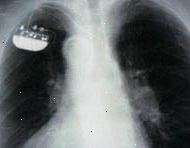

Zde je zobrazen hrudníku x-ray. Velký, bílý prostor ve středu je srdce. Tmavé prostory na obou stranách jsou plíce. Malý objekt v pravém horním rohu je implantovaný kardiostimulátor.